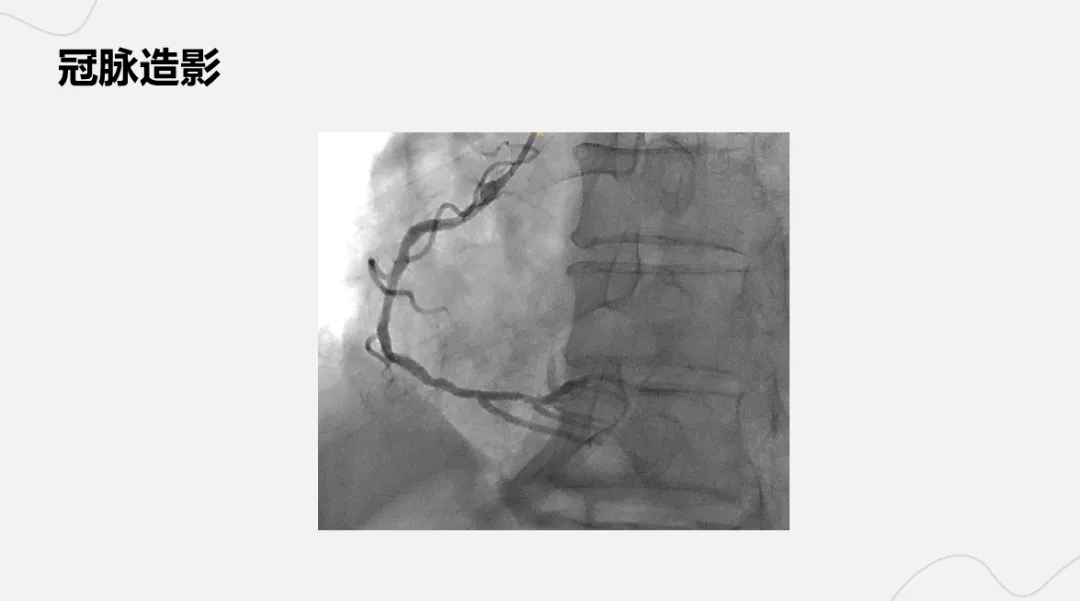

病例名称:诡异的非ST段抬高型心肌梗死